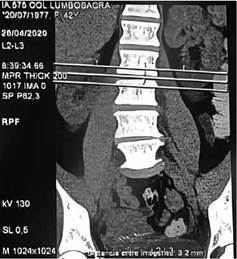

Paciente femenina de 42 años de edad que inicia con dolor en muslo derecho posterior a haber realizado sentadillas con una roca de un peso de 20 kilos aproximadamente, se sospecha desgarro muscular por el cuadro referido y se inicia tratamiento con diclofenaco sódico 50 mg cada 8 horas; sin embargo la semana siguiente el dolor se intensifica abarcando ya espalda baja y pierna derecha el cual no cede con el uso de AINES por lo que acude a consulta médica, se realiza ecografía de partes blandas en glúteo y muslo derechos la cual reporta focos de contractura de musculo glúteo medio izquierdo, entesis del tendón de fascia lata derecha y se deja tratamiento con tramadol 50 mg cada 12 horas, además de ketorolaco 60 mg a requerimiento ya que el dolor tenía una intensidad alta, hay un incremento del dolor los 3 días posteriores con un EVA 8/10 pese a medicación y se suma espasmos en músculos de muslo derecho que le impide realizar sus actividades diarias, por lo que se decide realizar TAC simple de columna lumbosacra donde se evidencia fractura por avulsión del muro posterior de L4, además de signos artrosicos facetarios bilaterales L4/L5.

Fig 1. TAC de columna lumbar: corte coronal de tomografia con ventana para plano blandos, evidencia escoliosis levoconvexa con disminución en la altura de discos en todos los niveles

En la tomografía se pueden observar estos cambios de forma más precoz que con la radiografía simple, con mayor detalle anatómico, ya que la destrucción ósea es más fácilmente evidenciable, además de ser esta superior a la IRM en la visualización de secuestro e involucro por la identificación de los márgenes. 6-7 Sin embargo, la sensibilidad es del 67% y la especificidad del 50%, es decir aun es baja para el diagnóstico de la patología. En el caso la tomografía no nos fue útil en el diagnóstico de las colecciones descritas en la resonancia.7